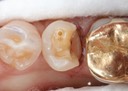

Alan Chinn #20 casting